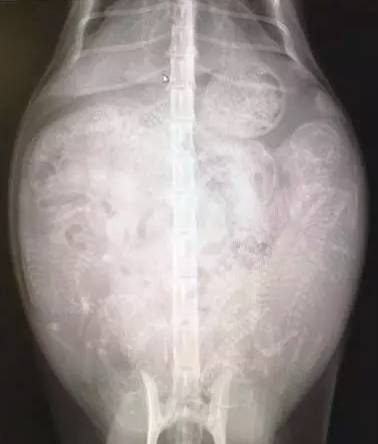

3、猫妈腹部逐渐涨大,此时不要进行腹部触诊,这样可能会造成胎儿的严重伤害。当然,受过专业训练的兽医可以这样进行检查。